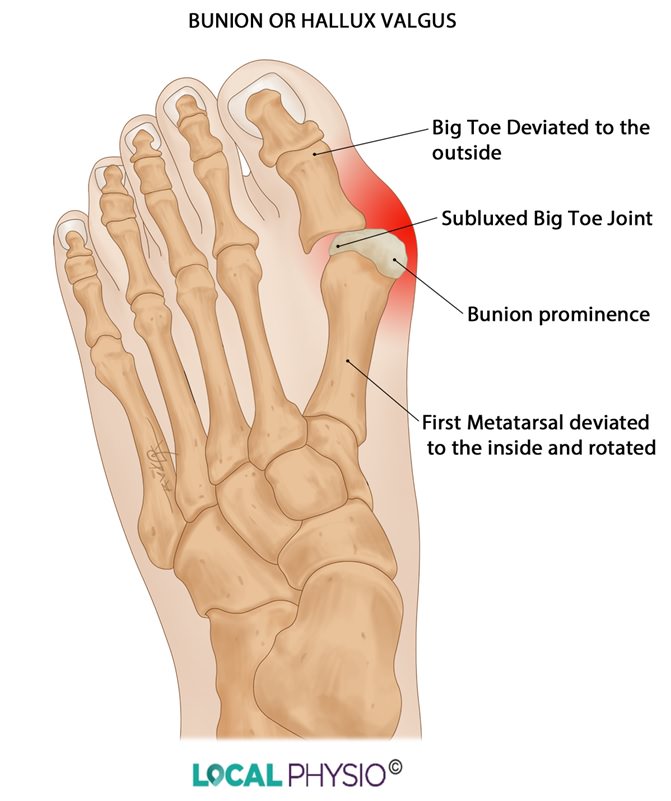

Рентген после операции Hallux valgus